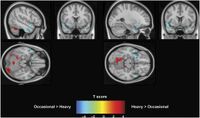

January 2, 2025 - In this study of young adults, lifetime history of heavy cannabis use was associated with lower brain activation during a working memory task. These findings identify negative outcomes associated with heavy lifetime cannabis use and working ...

November 20, 2025 - Large study examined the effects of cannabis use on 1,000 adults. Researchers found 63% of heavy cannabis users exhibited reduced brain activity on a task.